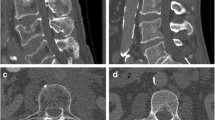

Virtual lowering of tube current and sparse sampling were successfully achieved in all patients (Figs. 1 and 2). A median of eight vertebrae (range 4–19 vertebrae) was captured by the FOV of MDCT scans, which covered the cervical spine in 20.0%, the cervico-thoracic spine in 8.6%, the thoracic spine in 5.7%, the thoraco-lumbar spine in 28.6%, and the lumbar spine in 37.1%. The average volumetric CT dose index recorded in the dose reports was 11.7 ± 5.7 mGy for original MDCT scans (Table 1), and was amounted 5.9 mGy, 2.9 mGy, and 1.2 mGy for MDCT with virtually lowered tube current or sparse sampling at 50%, 25%, and 10% of original data, respectively.

Virtual tube current reduction and sparse sampling in multi-detector CT (MDCT) of the thoracic and lumbar spine. Sagittal slices derived from full-dose MDCT (D100 P100), MDCT with virtually lowered tube current (D50 P100, D25 P100, and D10 P100), and MDCT with sparse sampling (D100 P50, D100 P25, and D100 P10) are shown in a patient with five thoracic fractures (T3, T6, T8, T10, and T11)

Overall image evaluation

Both virtual tube current reduction and sparse sampling led to decreased overall image quality, increased overall artifacts, and reduced contrast of vertebrae according to the evaluation of both readers (Table 3, Figs. 1 and 2, Supplementary Fig. 1). The assessed parameters were significantly different in MDCT with virtually lowered tube current and sparse-sampled datasets as compared to those in D100 P100 (p < 0.001; D100 P100 vs. D50 P100/D25 P100/D10 P100 and D100 P100 vs. D100 P50/D100 P25/D100 P10 of both readers).

When comparing MDCT with virtually lowered tube current to sparse-sampled datasets for overall image quality, sparse sampling resulted in significantly better scores according to each reader for all comparisons (p < 0.001, D50 P100 vs. D100 P50, D25 P100 vs. D100 P25, and D10 P100 vs. D100 P10 of both readers; Table 3 and Fig. 3). Similar findings with better scores for sparse-sampled imaging than for MDCT with virtually lowered tube current were observed for overall artifacts (p < 0.001, except for D50 P100 vs. D100 P50 for R2: p = 0.20; Table 3 and Fig. 3) and contrast of vertebrae (p < 0.001, except for D25 P100 vs. D100 P25 for R2: p = 0.005; Table 3 and Fig. 3). Good interreader agreement was observed for overall image quality, overall artifacts, and contrast of vertebrae, respectively (ICC > 0.80, R1 vs. R2 for D50 P100/D25 P100/D10 P100 and D100 P50/D100 P25/D100 P10; Table 3).

Fracture evaluation

Virtual tube current reduction by 50% of original current (D50 P100) allowed for correct detection of 100% (R1) and 95.8% (R2) of vertebral fractures when compared to original MDCT. Further lowering to 10% of original current (D10 P100) resulted in correct detection of 79.2% (R1) and 87.5% (R2) of vertebral fractures (Table 4). Sparse-sampled MDCT with 50% of the original projections (D100 P50) allowed for correct detection of all vertebral fractures by both readers as compared to original MDCT. Further decreasing the number of projections down to 10% of the original data allowed for correct detection of 95.8% (R1) and 91.7% (R2) of vertebral fractures (Table 4).